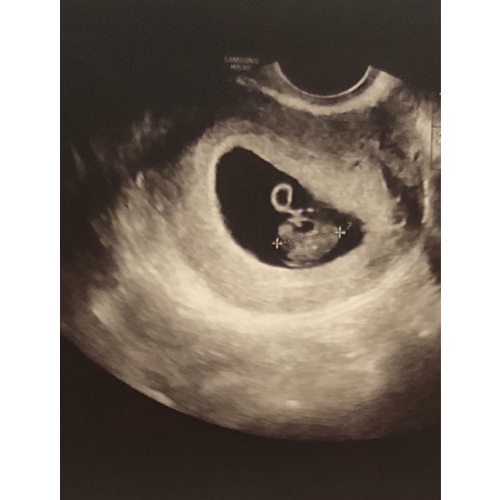

Volgens de Ramzi methode wordt er op deze manier voorspelt welk geslacht je krijgt.

Ligt je placenta aan de linkerkant van je lichaam?

Dan verwacht je waarschijnlijk: een meisje!

Bevindt je placenta zich aan de rechterkant van je lichaam?

Dan groeit er in je buik waarschijnlijk: een jongen!

Placenta ligt rechts

Volgens de methode zou je dan een jongen krijgen

Het is jammer dat je niet hebt gevraagd welke kant de placenta zit. Want het kan namelijk zijn dat de echo gespiegeld word weer gegeven.

Inwendige echo: Zie je op de uitdraai van een inwendige echo de lichte vlek rechts in de baarmoeder? Dan verwacht je volgens de Ramzi-theorie een jongen. Wanneer je hem links in de baarmoeder ziet, zou je van een meisje in verwachting zijn.

Uitwendige echo: Als de echo via je buik is gemaakt, is de echo gespiegeld. Zie je op de uitdraai van de echo de lichte vlek rechts? Dan zou dit betekenen dat je een meisje krijgt. Een lichte vlek aan de linkerkant wijst bij een uitwendige echo op een jongen.

Na aanleiding wat hierstaat zou je inderdaad een jongen krijgen.